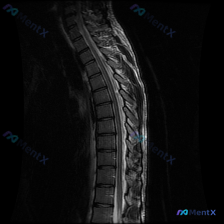

看到一份有意思的胸椎MRI读片病例,整理了一下资料和分析思路,和大家分享一下。 病例影像基本信息 这是一份胸椎MRI T2序列矢状位影像,扫描范围覆盖胸椎主要节段,图像质量好无明显伪影。 影像核心所见 1. 整体结构:胸椎保持正常生理性后凸,无明显侧弯、椎体滑脱,序列完整 2. 椎体与椎间盘:各椎体...